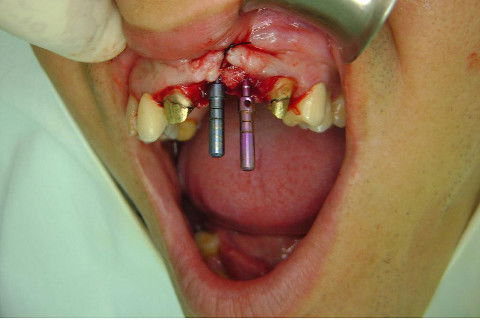

Cirurgia realizada hoje de manhã...No planejamento percebi medindo espessura do rebordo com especímetro que as medidas não estavam muito boas, ou o ideal, em torno de 4,5 a 5 mm ate´o terço médio do rebordo e melhorava no final, com 6 a 7 mm. Optei então por uma pequena expansão usando os expansores rosqueáveis. Aconteceu uma pequena fenestração na hora da fixação dos implantes, especialmente na região do 22 que fraturou o início da tábua óssea, mas não me preocupei porque não foi mais do que 2 mm de fratura em direção apical, o implante ficou infraósseo e com boa estabilidade (60 N no 21 e 40 N no 22). Esta fratura tb não deixou osso completamente solto, foi do tipo galho verde, deixei em posição e suturei normalmente. Só não fiz e nem estava planejado carga imediata mesmo, mais pelo motivo da oclusão inadequada do caso.

Fotos do caso